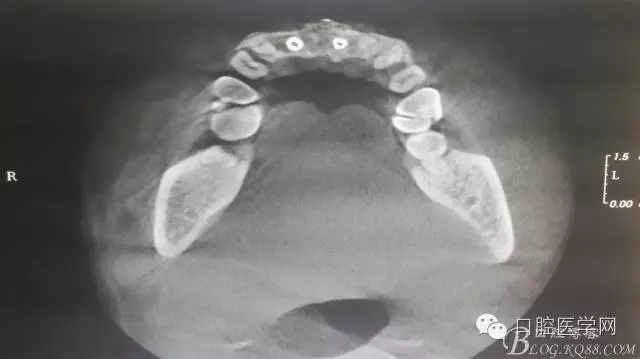

為他院轉(zhuǎn)診患者。男,無吸煙史,前牙因齲壞治療后,外力折斷導(dǎo)致拔除?,F(xiàn)拔除該牙后兩個多月。 左上區(qū)域骨寬度不足,計劃植入種植體同期GBR。

左上區(qū)域骨寬度不足,計劃植入種植體同期GBR。

植入種植體左側(cè)3510,右側(cè)4010,植骨Bioss,蓋膜Cytoplast。骨膜減張垂直褥式縫合加間斷縫合。